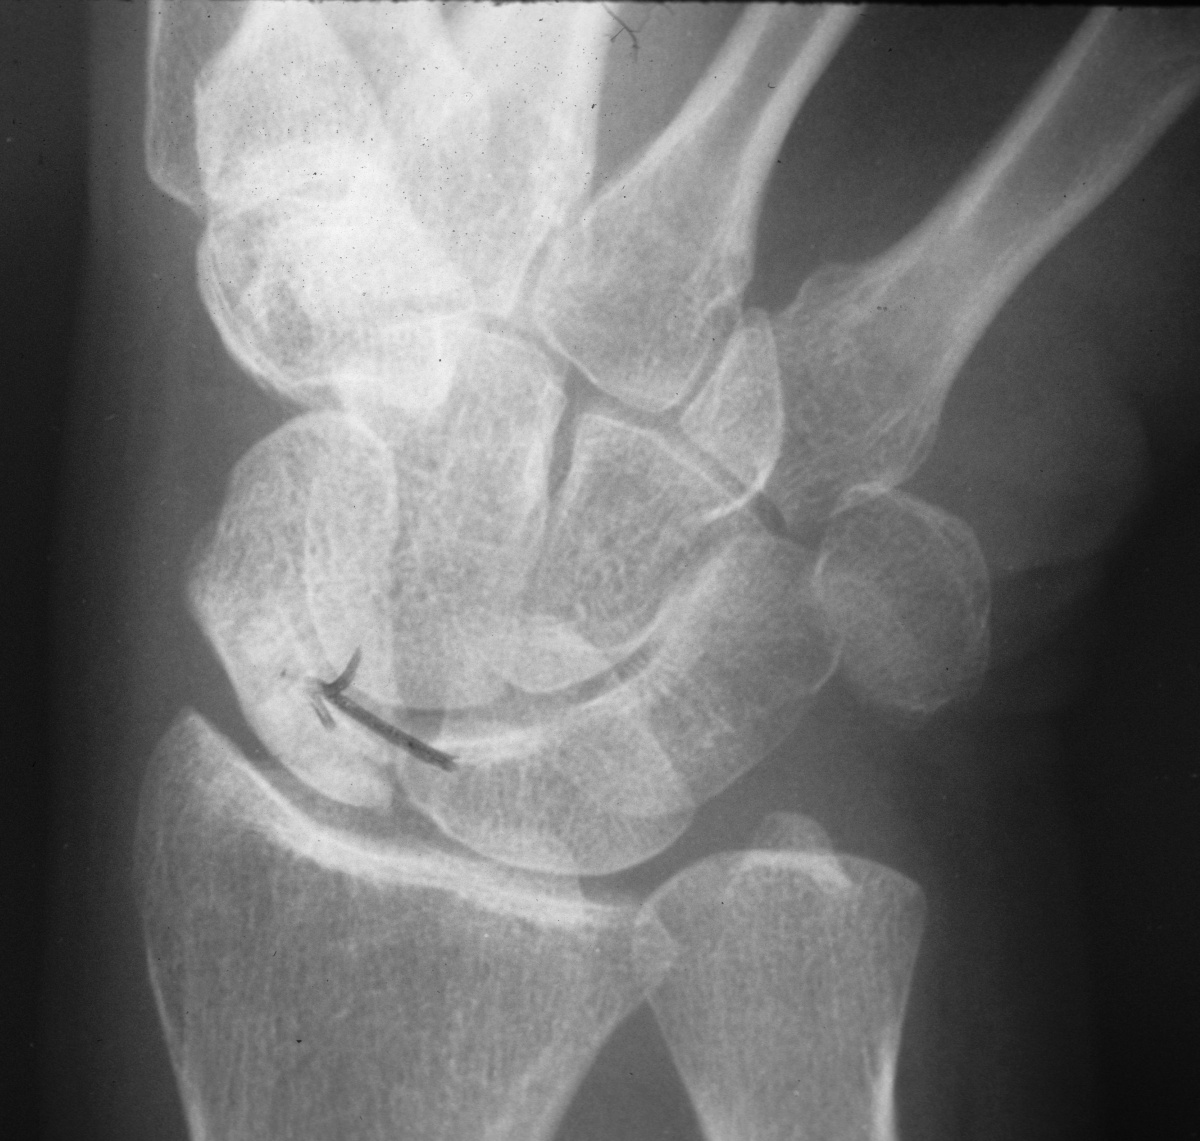

| Case 2. (Case of Charles Melone MD) This patient presented with a pathologic scaphoid fracture associated with an osteoid osteoma. |

| This was managed with

scaphoid excision and 4 corner fusion. The patient was given oral

tetracycline preoperatively to aid in tumor marking. This view is

of the distal scaphoid, looking at the fracture line. |